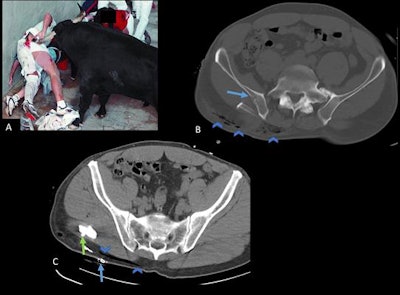

"We had a case in which five bulls had run over two men. One of them was admitted with severe trauma involving deep, important cutaneous emphysema spreading from the pelvis all the way up to the cervical vertebrae. CT showed additional rib fractures and rib fragment displacement into the thorax cavity," he said.